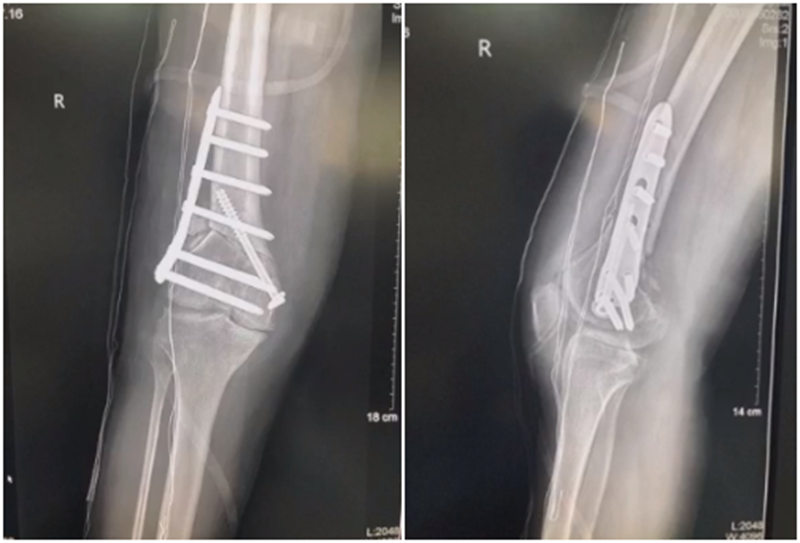

(2)术后力线丢失

对于力线丢失原则是重新矫正力线,重新固定,通常在合页端加上内固定物,主要目的是为了抗旋,有一些截骨端还需要进行植骨。术后早活动晚负重。

病例,X患者,女,双侧外翻膝,行双侧DFO。

术后6周摔伤,一侧出现膝内翻。

影像学检查显示左侧出现合页断裂。

进行翻修,术前力线显示内翻。

术中发现螺钉松动,截骨端出现坎插迹象。

近端螺钉松开,调整力线,重新固定后,在外侧加小钢板抗旋。

术后10周复查,力线较好。